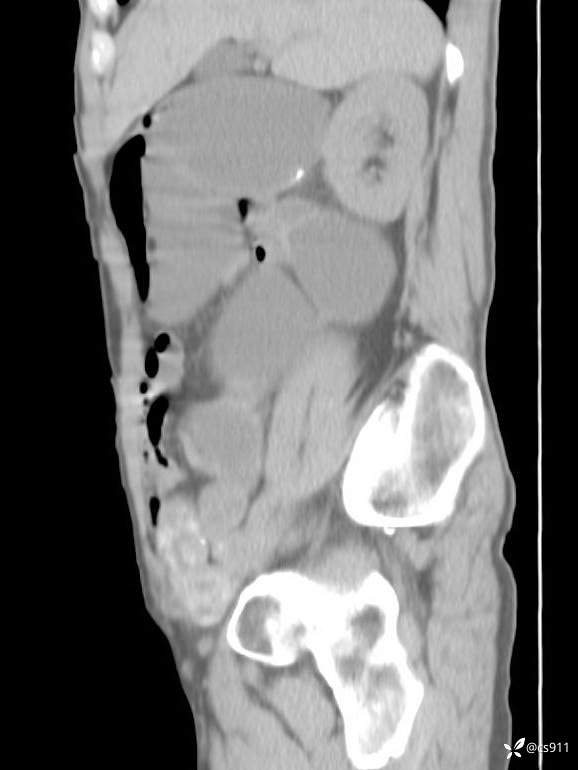

急腹症之急诊CT,原因?答案公布

男,77岁,腹痛、腹胀伴恶心呕吐1天。呕吐胃内容物,非喷射性呕吐,有咖啡色样胃内容物,诉有胃穿孔病史。查体:全腹平,下腹部压痛,全腹无反跳痛,叩诊呈浊音,移动性浊音阴性,肠鸣音减弱,1-2次/分。肛检:直肠未扪及明显肿物,可触及大量粪块。

T 36.6℃ P 80次/分 R 26次/分 BP 100/60mmHg

白细胞(WBC) H 14.55 10e9/L 4-10

中性粒细胞百分率(NEUT%) H 85.7 % 40-75

血淀粉酶(AMY) HH 1859 U/L 35-135

癌胚抗原(CEA) H 27.44 ng/ml 0-5

呕吐物 潜血试验 * 阳性 阴性

患者轮椅入室检查神志清楚, 能配合摆位和呼吸